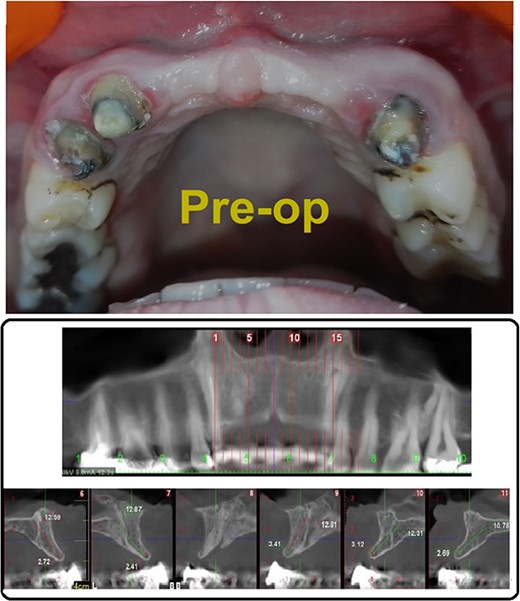

A 33-year-old medically fit female patient came to the dental care center suffering from missing teeth in the upper anterior region (11, 21, 22). During clinical and radiographic examinations, severe bone resorption was observed. Alveolar bone thickness ranged from 2.4 to 3.4 mm (Class IV according to Tolstunov classification for alveolar ridge defects [13]), (Fig. 1A and B) gingival thickness was moderate (1 mm). After discussing all treatment options with the patient, the treatment was planned in two stages. The first stage, horizontal bone augmentation using bone allograft in combination with C-PRF. The second stage, implant surgery after 5 months from the first stage.